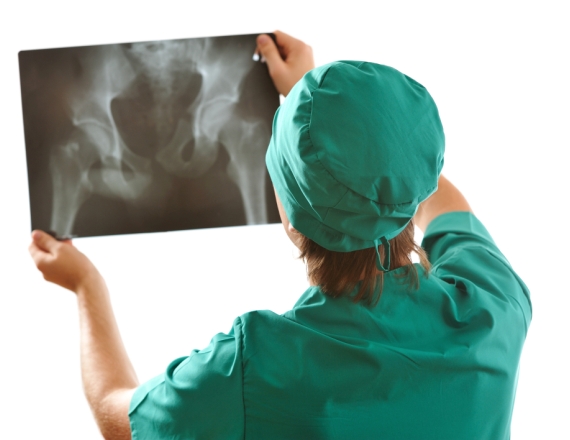

רנטגן

עצם הזנב

מאזין בן 70: "החלקתי במדרגות ושברתי את עצם הזנב. כיצד ניתן לטפל בשבר?"